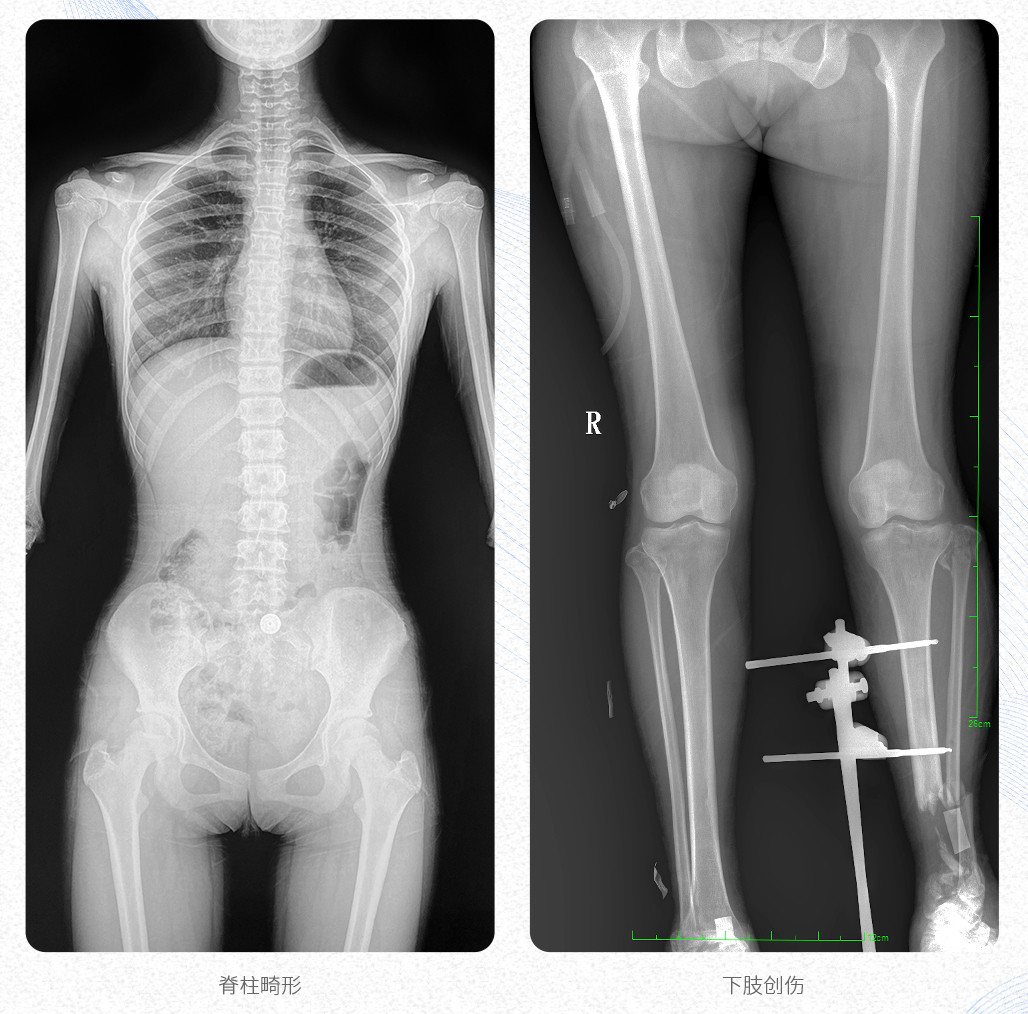

新品PLX8600大視野平板動(dòng)態(tài)DR產(chǎn)品說明:

? ? 普愛醫(yī)療新推出自主研發(fā)的大視野平板動(dòng)態(tài)DR——PLX8600,專為臨床大視野需求打造,圖像不拼接,可有效簡(jiǎn)化影像科室檢查流程,提升工作效率,提高診斷精度,降低臨床拍攝劑量。